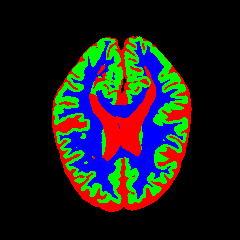

• OASIS-1 [34]: Derived from the Open Access Series of Imaging Studies, this dataset comprises T1-weighted MRI scans from 421 subjects (aged 18–96). The images were acquired with a resolution of 176×208176\times 208 pixels and a slice thickness of 1.25 mm (TR=9.79.7 ms, TE=4.04.0 ms, TI=2020 ms). Following standard protocols, we utilize the provided manual segmentation masks for Cerebrospinal Fluid (CSF), Grey Matter (GM), and White Matter (WM).

7 Qualitative Evaluation

Fig. 8 and Fig. 10 provide qualitative comparisons on the OASIS-1 and MRBrainS13 datasets, respectively. It is visually evident that the baseline predictions (c) and standard augmentations (e.g., (d), (g), (i)) frequently suffer from noisy artifacts, blurred boundaries, and mis-segmentation of intricate anatomical structures. In stark contrast, our ”Ours+” enhanced methods (e.g., (e), (h), (k)) consistently produce segmentation maps that are visibly cleaner, more spatially coherent, and demonstrate significantly sharper adherence to the Ground Truth (b). This superior fidelity is particularly noticeable in the complex sulcal patterns and holds true across all three backbones (rows), confirming that our framework yields more robust and anatomically plausible results.